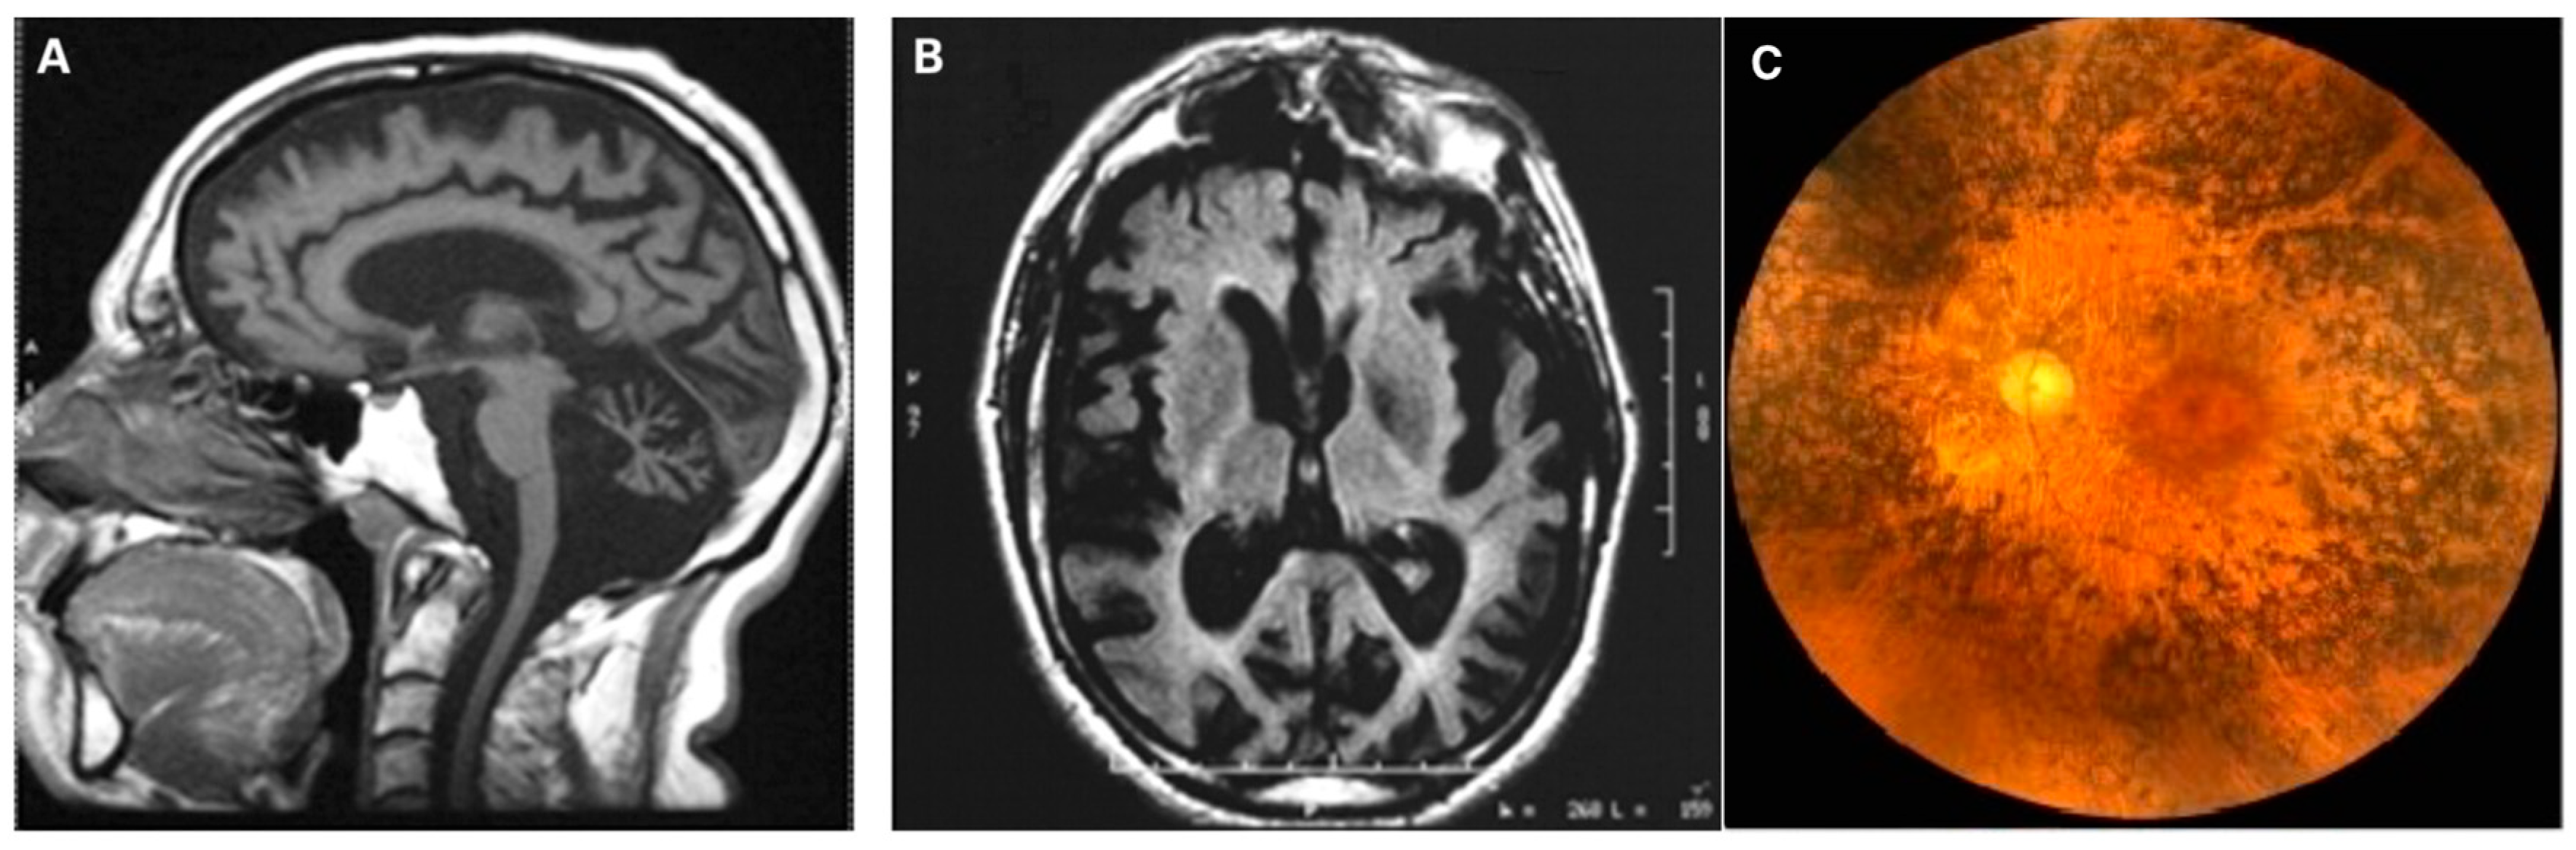

17. Syndromic Optic Atrophy

“Plus” Forms of LHON and ADOA